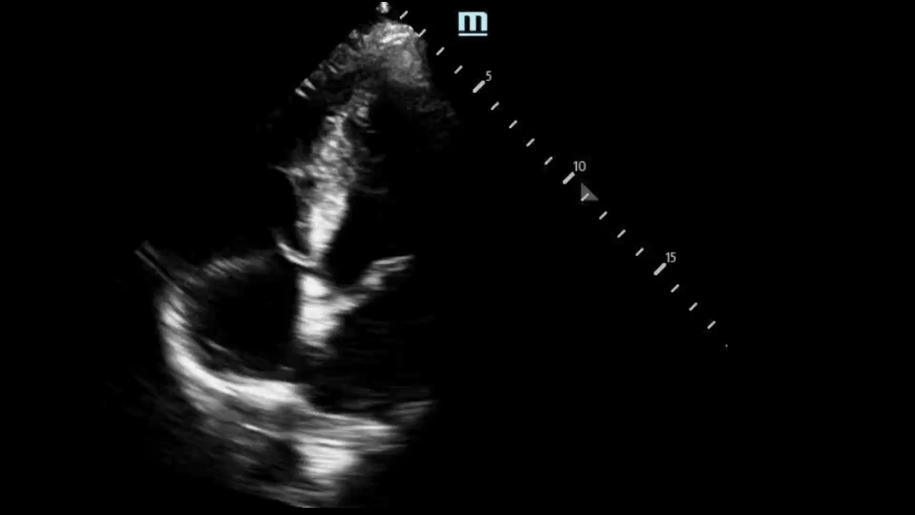

• View: A5 View with Continuous Wave Doppler

This is where you would place your Continuous Wave Doppler axis.